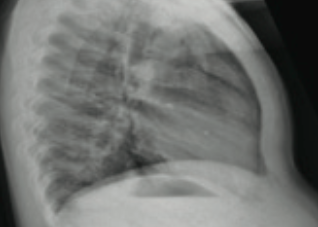

A 2-year-old boy presented to the emergency department with a persistent cough with production of green purulent sputum.

Case Report

A 6-year-old boy presented in the emergency department with difficulty breathing and chest pain.